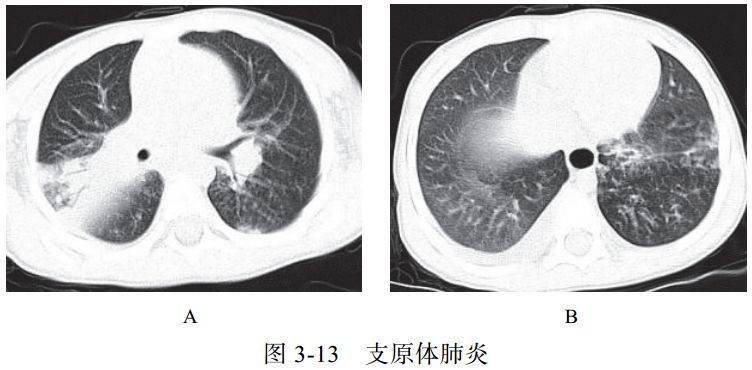

四、与肺部支原体感染的鉴别诊断

支原体肺炎是由支原体引起的以间质性改变为主的肺炎。支原体侵入肺内可引起支气管、细支气管黏膜及周围间质充血和水肿,多核细胞浸润,侵入肺泡可产生肺泡浆液性渗出炎症。病变范围可从小叶、肺段至大叶。多数患者症征不符:临床症状重,影像学表现较轻

实验室检查支原体抗体呈阳性,发病 2~3 周后血冷凝集试验比值升高(可达 1∶64)

影像学表现:

(1) HRCT 显示更清晰,呈树雾征(图 3-13A)、树芽征(图 3-13B),可出现支气管壁增厚

(2)渗出实变较淡,常合并支气管肺炎